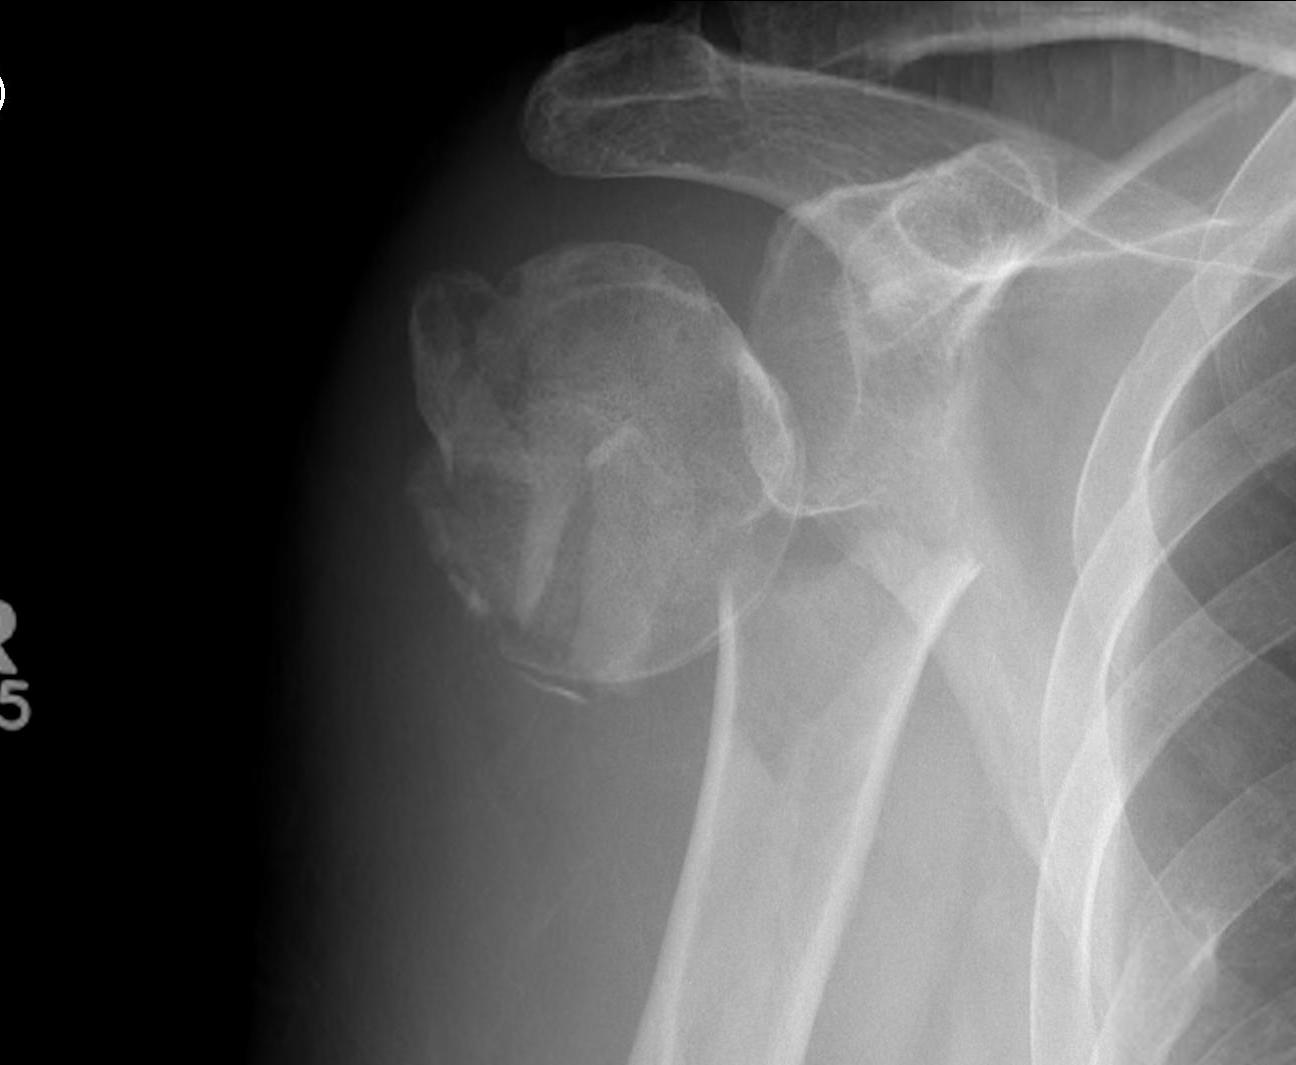

proximal humerus fracture Background ORIF with locking plate Arthroplasty Greater tuberosity fractures Lesser tuberosity fractures / avulsions Book traversal links for Proximal humerus fractures ‹ Pectoralis Major Tears Up Background ›